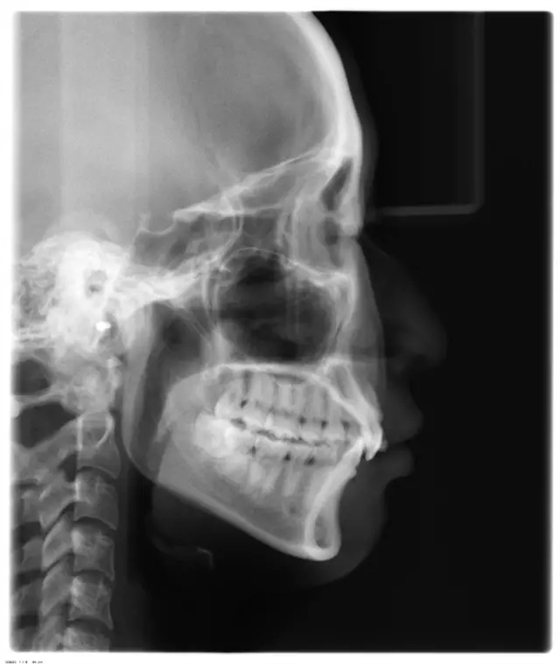

Damon 病例分享:安氏 II 類二分類露齦笑的矯治(董一磊)

上下牙列擁擠,磨牙尖牙Ⅱ 類關(guān)系,3 度的深覆牙合,上頜中切牙伸長內(nèi)傾拔除上頜雙側(cè)的第一前磨牙,先粘上頜高轉(zhuǎn)矩的自鎖托槽排齊牙列,唇向開展上頜切牙,有一定的覆蓋,粘下頜標準轉(zhuǎn)矩托槽,上頜 1, 2 之間植入種植支抗壓入,同時后牙 5, 6 之間植入種植支抗內(nèi)收前牙,打開咬合關(guān)閉間隙。治療關(guān)鍵:前牙轉(zhuǎn)矩的控制第 1 個月 上頜粘上 Damon Q 高轉(zhuǎn)矩托槽,上 .014 熱激活 NiTi 絲。第 3 個月 上換 .014 x .025 熱激活 NiTi 絲。第 5 個月 上頜基本排齊,覆蓋增大,上換 .017 x .025 NiTi絲,下頜粘托槽,下 .014 熱激活 NiTi 絲。第 7 個月 上 .017 x .025 NiTi 絲加搖椅,下?lián)Q .014 x .025 熱激活 NiTi 絲第 9 個月 上頜換 .019 x .025 NiTi 絲加搖椅,下頜換 .017 x .025 NiTi 絲第 11 個月 下頜換 .019 x .025 加搖椅,上頜 1, 2 之間, 5, 6 之間植入種植釘,下頜出現(xiàn)散隙。第 13 個月 上頜換 .019 x .025ss 加搖椅,前牙種植釘用 Power Chain 壓低前牙(每側(cè) 100g),后牙種植釘關(guān)閉間隙(每側(cè) 150g),下?lián)Q .019 x .025ss,Power Chain 關(guān)閉間隙。第 19 個月 上頜前牙基本壓低到位去除前牙種植釘,繼續(xù)用關(guān)閉間隙,下頜散隙關(guān)閉。

第 22 個月 上頜覆蓋變小,去除 5, 6 之間種植釘,后牙前移關(guān)閉間隙。第 30 個月 患者未配合中線牽引,下中線仍有 1mm 右偏,患者對矯治效果滿意要求拆除,拆除固定矯治器,取模制作壓模保持器。 1.骨性 Ⅱ 類的患者內(nèi)收前牙時需對上頜前牙的轉(zhuǎn)矩進行較好的控制才能獲得良好的面型和唇部形態(tài)。 2.露齦笑的患者治療前要分析其病因是唇、牙齦、牙齒、牙槽骨、上頜骨或多種因素結(jié)合,再制定矯治方案。 3.Ⅱ 類第二分類伴露齦笑的患者的上頜前牙移動軌跡是唇向開展-壓低-整體內(nèi)收。 4.Ⅱ 類第二分類牙齒舌傾比較厲害的情況,上頜中切牙慎用樹脂咬合墊。 5.壓低前牙或控根移動時容易發(fā)生牙根的吸收,需輕力緩慢的移動。